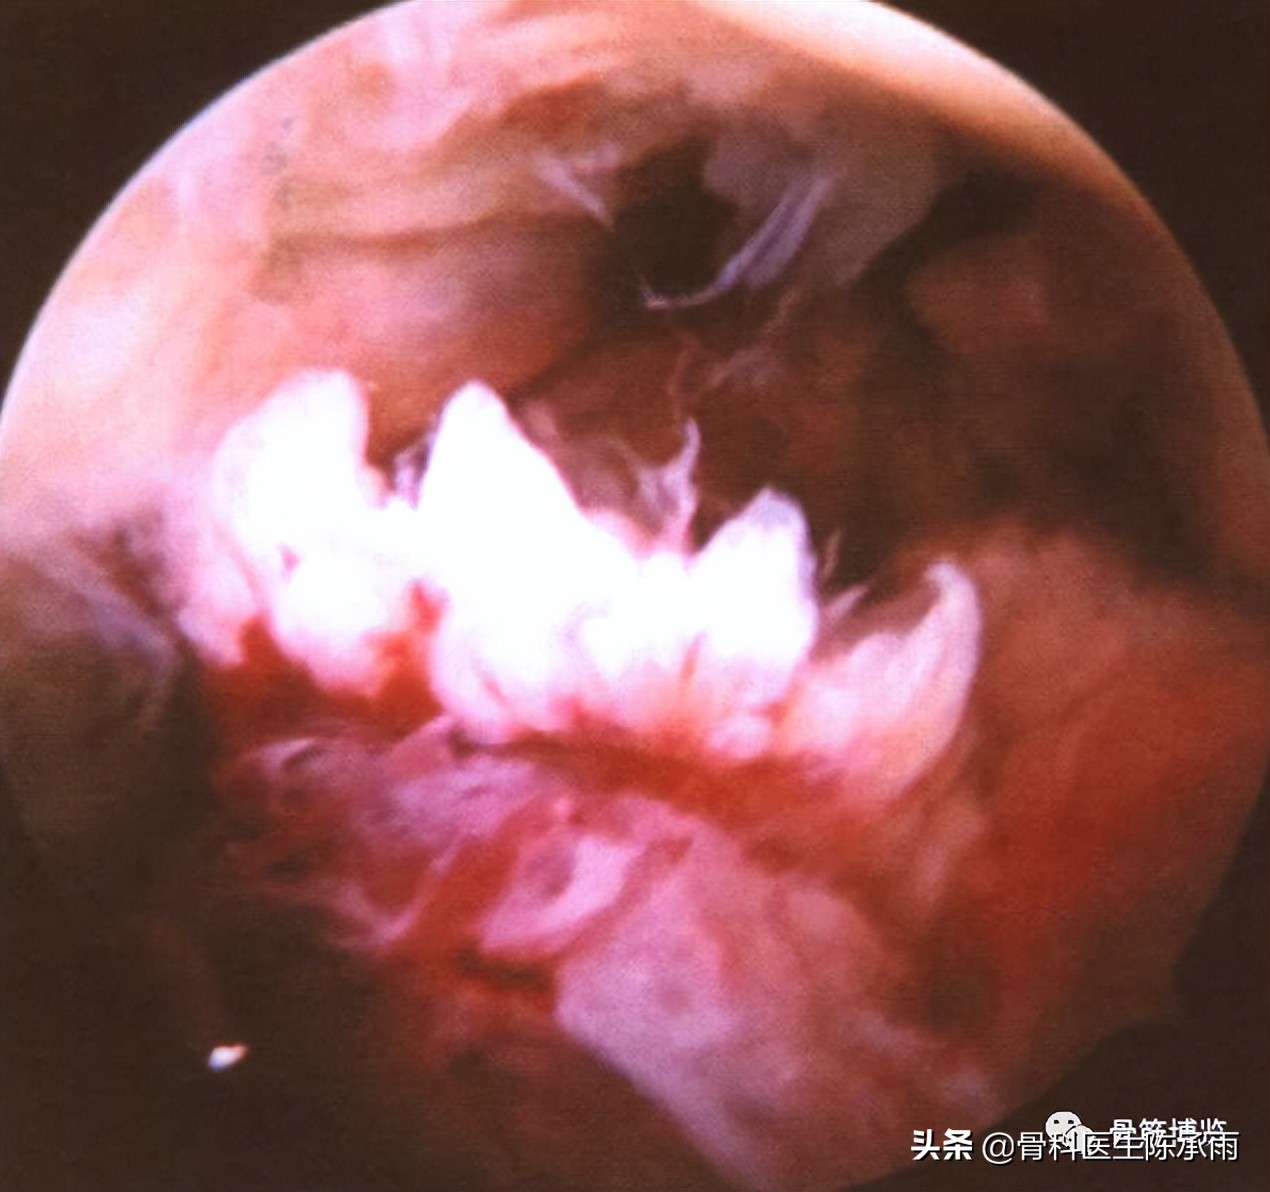

交叉韧带的损伤是较为严重的运动性损伤,其中以ACL损伤常见。ACL断裂多为韧带纤维连同滑膜一起撕裂,韧带断端多呈束状,有些可从止点处撕脱。少数病例,可出现滑膜内断裂,镜下不易发现断端,但可根据韧带滑膜组织充血、肿胀、瘀斑等间接改变判定,同时认真检查,可发现韧带张力明显减弱、松弛,并可通过滑膜损伤处将韧带断端纤维勾出,继而显露断端。ACL断裂,多发生在韧带的中上段,多为韧带实质部的损伤,上止点处撕脱损伤较少,应予以缝合修补。ACL的解剖薄弱易损部位位于韧带的中上区域。

前交又韧带断裂